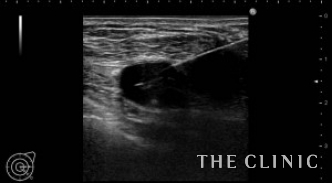

3年前に他院で脂肪注入による豊胸を受けられた方です。手術直後から痛みとしこりがあったとのことで、エコーにて右はオイルシストが1つ、左は混合性のしこりが2つあることを確認しました。

混合性のしこりは、ベイザーで崩して吸引除去します。オイルシストは穿刺吸引します。